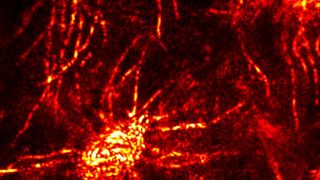

Despite its importance for speaking, breathing, and eating, relatively little is known about the genetic underpinnings of the human vocal tract. A consortium of geneticists, neuroscientists and linguists has estimated the heritability of many elements of the vocal tract based on 3D structural magnetic resonance imaging (MRI) in 632 monozygotic and dizygotic twins.